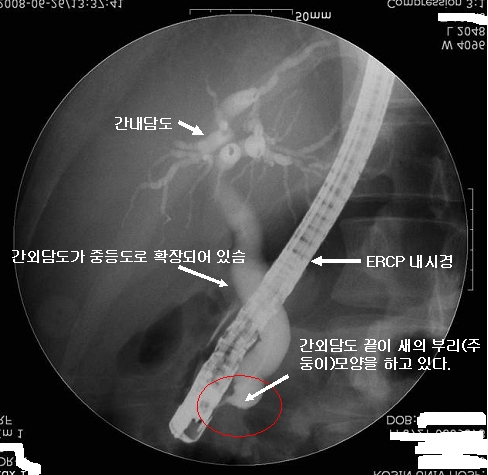

대한소화기학회

대한소화기학회 from www.gastrokorea.org